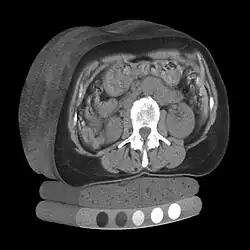

Quantitative computed tomography (QCT) is a medical technique that measures bone mineral density (BMD) using a standard X-ray computed tomography (CT) scanner with a calibration standard to convert Hounsfield units (HU) of the CT image to bone mineral density values.[1] Quantitative CT scans are primarily used to evaluate bone mineral density at the lumbar spine and hip.

In general, solid phantoms placed in a pad under the patient during CT image acquisition are used for calibration. These phantoms contain materials that represent a number of different equivalent bone mineral densities. Usually either calcium hydroxyapatite (CaHAP) or potassium phosphate (K2HPO4) are used as the reference standard.[2]

Originally, conventional 2D QCT used individual, thick CT slice images through each of multiple vertebrae which involved tilting the CT scanner gantry to align the slice with each vertebra. Today, modern 3D QCT uses the ability of CT scanners to rapidly acquire multiple slices to construct three-dimensional images of the human body. Using 3D imaging substantially reduced image acquisition time, improved reproducibility and enabled QCT bone density analysis of the hip.[1]